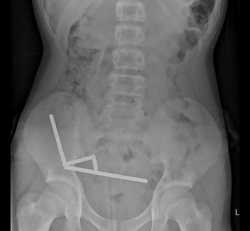

https://www.theguardian.com/world/2025/oct/24/surgeons-remove-high-power-temu-magnets-new-zealand-teenagers-intestines

>Surgeons remove Temu magnets from intestines

One of these fuckers tried to give themselves magic powers by swallowing Chinese magnets.